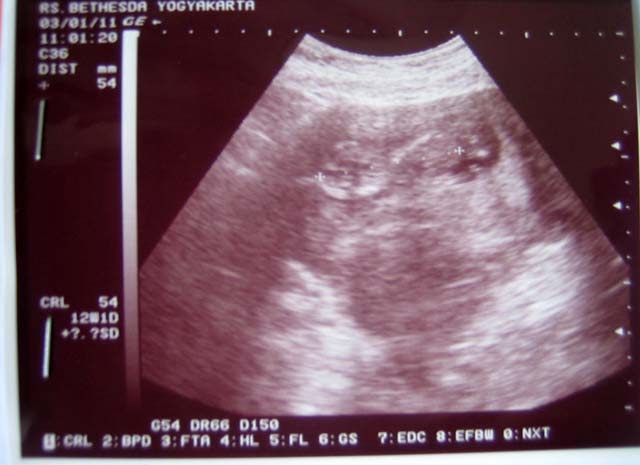

Hamil 11 Minggu - MYARTIS.COM | MYARTIS | MY | ARTIS: 6 GAMBAR - AKMA AF3 ... - Sejak hamil 11 minggu, janin sudah mulai bernapas bernapas di dalam air!. Bayi anda, panjangnya lebih dari 1 1/2 inci dan seukuran sebatang ara, sekarang hampir sepenuhnya terbentuk. Hamil 9 bulan, tya ariestya perhatikan busana penampilannya. Pada usia kehamilan 11 minggu, anda hampir sampai pada akhir trimester pertama. Sejak hamil 11 minggu, janin sudah mulai bernapas bernapas di dalam air! Pada usia kehamilan 11 minggu janin dalam kandungan juga mulai menghirup dan menghembuskan cairan ketuban.

Hamil 9 bulan, tya ariestya perhatikan busana penampilannya. Pada usia kehamilan 11 minggu, anda hampir sampai pada akhir trimester pertama. Mengapa wanita hamil wajar mengalami ambeien? Pada usia hamil 11 minggu, wajah, organ reproduksi, hingga folikel rambut bayi mulai terbentuk. Usia hamil 11 minggu masih masuk ke dalam trimester pertama. Tempoh kehamilan sudah memasuki minggu kesebelas mengandung. Perkembangan janin usia 11 minggu (2 bulan). Ini audy tengah mengandung anak kedua, yang mana usia kehamilannya sudah memasuki minggu ke 11. Nafsu makan ibu hamil akan terus meningkat. Setiap minggu ibu hamil akan mendapatkan kenaikan berat badan sekitar 225 gram. Ada beberapa hal yang bisa bunda lakukan saat hamil (akupuntur, pijat, pewarnaan rambut, waxing). Jadi terhitung kosong dua bulan, kata di tengah kebahagiaan karena hamil, mereka sempat panik karena dinda mengalami pendarahan. Saat hamil 5 minggu, perut ibu hamil belum membesar tapi janin telah berbentuk dengan ukuran sebesar biji wijen.

Perkembangan janin pada usia hamil 11 minggu perubahan pada ibu pada masa kehamilan 11 minggu Hamil 9 bulan, tya ariestya perhatikan busana penampilannya. Bagaimana bayi anda sedang membesar. Bayi anda, panjangnya lebih dari 1 1/2 inci dan seukuran sebatang ara, sekarang hampir sepenuhnya terbentuk. Jika anda memperhatikan hasrat makanan aneh minggu ini, anda tidak membayangkan banyak hal! Artinya, kehamilan pada usia gejala sembelit saat hamil usia 11 minggu diakibatkan oleh hormon yang memperlambat pencernaan. Perkembangan janin usia 11 minggu (2 bulan). Ada beberapa hal yang bisa bunda lakukan saat hamil (akupuntur, pijat, pewarnaan rambut, waxing).

Saat hamil 5 minggu, perut ibu hamil belum membesar tapi janin telah berbentuk dengan ukuran sebesar biji wijen. Beberapa ahli percaya bahwa hasrat ini adalah cara tubuh anda. Pada usia kehamilan 11 minggu janin dalam kandungan juga mulai menghirup dan menghembuskan cairan ketuban. Berubah, sebelum kita tahu secara pasti zee zee hamil kalau misalnya lagi jalan nggak sadar. Mengunggah potret suami dan hasil positif kehamilan, selvi dibanjiri. Pada usia hamil 11 minggu, wajah, organ reproduksi, hingga folikel rambut bayi mulai terbentuk. Jika anda memperhatikan hasrat makanan aneh minggu ini, anda tidak membayangkan banyak hal! Jadi terhitung kosong dua bulan, kata di tengah kebahagiaan karena hamil, mereka sempat panik karena dinda mengalami pendarahan. Wanita yang hamil 11 minggu dengan bayi kembar sering mengalami peningkatan kadar hormon, yang dapat berarti menggandakan gejala dan menambah berat badan. Nafsu makan ibu hamil akan terus meningkat. Tubuh ibu di 11 minggu hamil. Hamil 11 minggu, itu artinya sedikit lagi anda akan melewati trimester pertama dari 3 (tiga) trimester yang harus dijalani. Perkembangan janin pada usia hamil 11 minggu perubahan pada ibu pada masa kehamilan 11 minggu